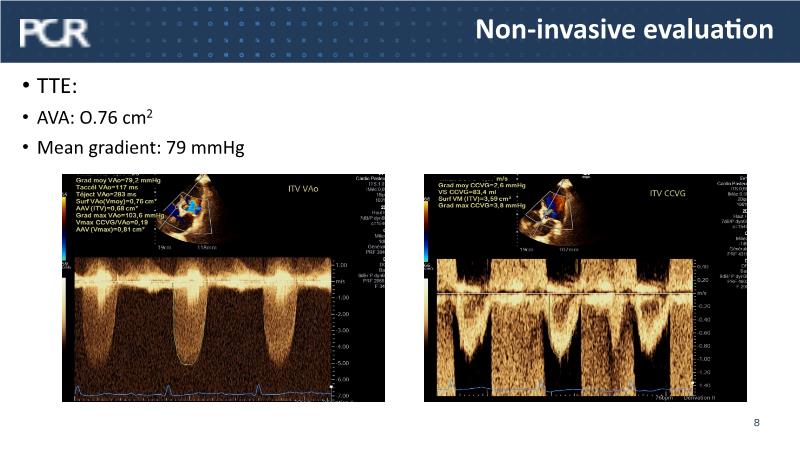

- To learn from the experts best-in-the-class TAVI practice: pre-procedural (Imaging, sizing rationale, treatment strategy), procedural tips and tricks and post-procedural management